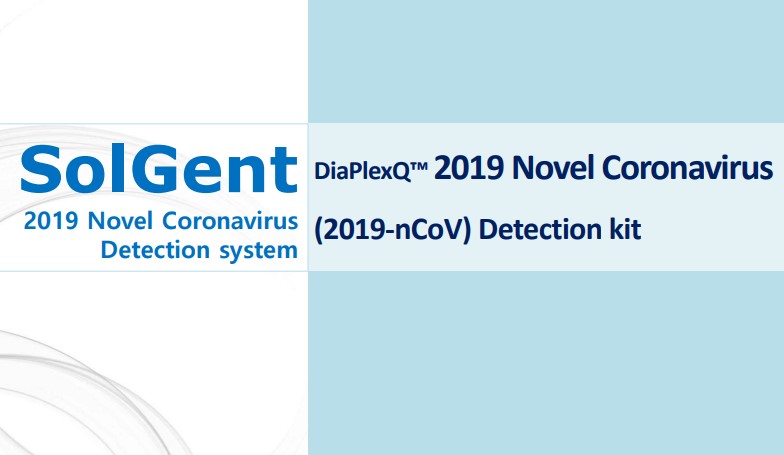

SGTI Flex COVID-19

SGTI Flex COVID-19

COVID-19, speedy and sustainable community spread even without identifying exactly who and how to spread.